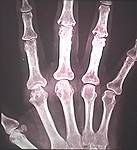

Abatacept (Orencia®) hemmte in dieser Studie effektiv die strukturellen Veränderungen an den Gelenken bei Patienten mit rheumatoider Arthritis.

In vielen Langzeitstudien ist der Zusammenhang zwischen dem Ausmaß der radiologisch sichtbaren Gelenkschäden und der körperlichen Funktionsfähigkeit bei rheumatoider Arthritis (RA) untersucht worden. Eine Auswertung der TEMPO-Studie mit Etanercept (Enbrel®) und Methotrexat hat jetzt gezeigt, dass auch Patienten mit kürzlich festgestelltem progredienten Verlauf der Gelenkzerstörung unter eine stärkeren körperlichen Behinderung leiden.